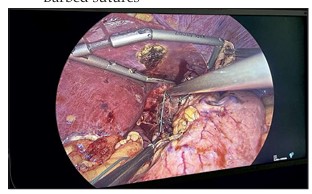

Nissens Fundoplication: A Laparoscopic Edge?

Background: Hiatal hernia often leads to gastroesophageal reflux disease (GERD), which may be refractory to medical therapy. Surgical intervention in the form of Nissens fundoplication can provide definitive relief. With advancements in minimally invasive techniques, the role of laparoscopic Nissens fundoplication is increasingly prominent. Aim: To compare the effectiveness of open versus laparoscopic Nissens fundoplication in patients with endoscopically confirmed hiatal hernia. Objectives: • Compare operative time, symptom relief, and complications in open and laparoscopic procedures. • Evaluate improvement using De-Meester Johnson reflux score. Material: A prospective study involving 38 patients (18-60 years) at a tertiary care hospital over 18 months (Sep 2022 - Mar 2024). Patients were randomized into two equal groups for open or laparoscopic Nissens fundoplication. Results: Both groups showed significant symptomatic improvement. Laparoscopic surgery had a longer operative time (135 vs 110 minutes) but fewer complications and better De-Meester scores Post-operatively. Statistically significant improvement in heartburn, regurgitation, and dysphagia was observed, especially by Postoperative day 7. Conclusion: Laparoscopic Nissens fundoplication is as effective as open surgery in relieving GERD symptoms, with additional benefits of fewer complications and faster recovery, despite longer operative duration.